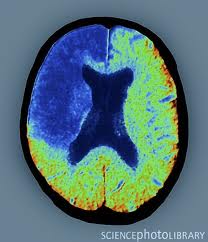

A stroke is a kind of brain injury that may happen in various areas of the brain. It is more common in older adults, who are about 65 years-old and above. There are two types of stroke—ischemic and hemorrhagic. Ischemic stroke is when the blood vessels are blocked and oxygenated blood is prevented from reaching the brain and this causes damage. Hemorrhagic stroke is when the blood vessels in the brain rupture or burst because of fragility or extreme high blood pressure. This causes damage to the brain tissues because the oxygenated blood does not circulate in the brain anymore.